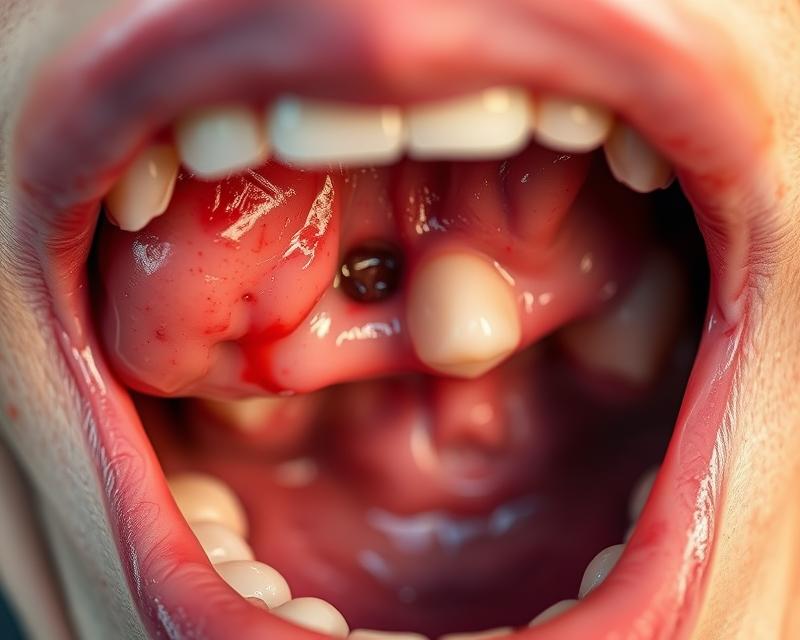

Ropnie w jamie ustnej to przykre stany zapalne, które objawiają się pojawieniem ropnych zmian w tkankach. Zwykle są wynikiem infekcji bakteryjnej, w której dochodzi do gromadzenia się ropy w miękkich tkankach lub pod kością. Te nieprzyjemne zmiany mogą wystąpić w różnych miejscach jamy ustnej, takich jak:

Główną przyczyną powstawania ropni są bakterie. Ich rozmiary mogą znacznie się różnić, a często towarzyszy im ból, obrzęk oraz zaczerwienienie otaczających tkanek. Jeśli nie zostaną odpowiednio leczone, mogą prowadzić do poważniejszych komplikacji, takich jak rozprzestrzenienie infekcji na inne obszary organizmu.

Ropień to obszar, gdzie gromadzi się ropa w wyniku infekcji. Organizm reaguje na obecność bakterii, co prowadzi do stanu zapalnego, a objawy obejmują obrzęk i zaczerwienienie tkanek w okolicy zmiany. Wydzielina ropna, która może pojawić się z ropnia, zazwyczaj sygnalizuje nasiloną infekcję, która wymaga pilnej interwencji stomatologicznej. Z mojego doświadczenia wynika, że zbagatelizowanie tych symptomów często prowadzi do poważniejszych problemów zdrowotnych.

Diagnostyka ropni w jamie ustnej koncentruje się na analizowaniu objawów klinicznych oraz lokalizacji ropnia. Na początku lekarz stomatolog przeprowadza szczegółowy wywiad z pacjentem, a następnie dokładnie bada jamę ustną. Objawy, takie jak ból, obrzęk czy obecność ropnego wysięku, są niezbędne do postawienia prawidłowej diagnozy.